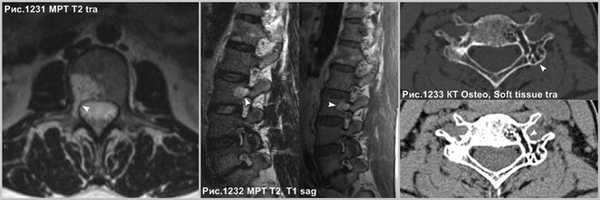

В случае нахождения гемангиомы в дужке или распространения с тела в дужку позвонка (головки стрелок на рис.1231-1233), важно указывать данный факт в связи с тем, что структура позвонка в указанном месте ослаблена и может послужить причиной патологического перелома в процессе медицинских манипуляций, так же важно учитывать этот факт нейрохирургам при транспедикулярной фиксации.

Осложнение в развитии гемангиом в виде экспансивного роста, что встречается не часто, когда опухоль (звёздочки на рис.1228,1229) распространяется за пределы тела позвонка (головки стрелок на рис.1228,1229), приводит к компрессии спинного мозга (стрелки на рис.1228, 1229). Серьёзное осложнение представляет собой патологический перелом тела позвонка (головки стрелки на рис.1230), структура которого была ослаблена разряжением губчатого вещества в процессе роста гемангиомы.